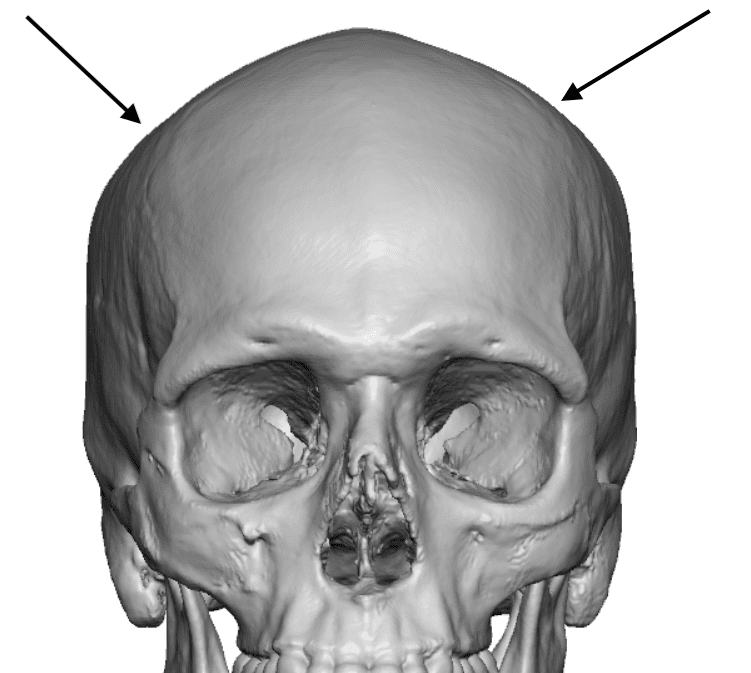

Desire for an improved head shape so that it looks rounder and not so peaked or sloped.

Placement of custom skull implant for parasagittal augmentation to create a rounder head shape. An example of what appears to be a high sagittal crest that is really low parasagittal skull areas.

Desire for an improved head shape so that it looks rounder and not so peaked or sloped.

Placement of custom skull implant for parasagittal augmentation to create a rounder head shape. An example of what appears to be a high sagittal crest that is really low parasagittal skull areas.